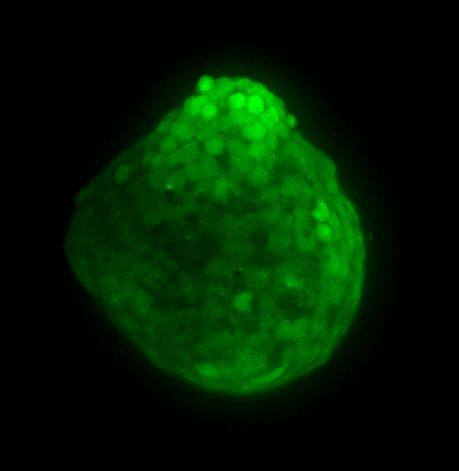

为了生成 3D 球体,将 NCI-H460 细胞(源自非小细胞肺癌)以两种不同的密度接种在超低吸附培养板中:3×103 个细胞/孔或 700 个细胞/孔。在直径分别达到约 400-500 或 150-200 um 后,用细胞毒素剂处理球体 6 天。通过使用钙黄绿素 AM 和碘化丙啶 (PI) 的活/死染色来观察和评估药物的效果。钙黄绿素 AM 是一种细胞渗透性染料,用于测定细胞活性。非荧光钙黄绿素 AM 在活细胞中被细胞内酯酶水解后转化为(绿色)荧光钙黄绿素。PI 是一种红色荧光核染色剂,通常用于检测死亡细胞,因为它不能进入完整的活细胞。最后,使用 Hoechst 染料将细胞核染成蓝色。

我们采用 CrestOptics X-Light V3 转盘共聚焦结合 Prime BSI 相机(Photometrics,像素尺寸 6.5 um)进行采集。我们比较了使用 20 倍空气物镜(CFI Plan Apo Lambda,尼康,0.7 NA 和 1mm WD)和 25 倍硅油物镜(CFI Plan Apo Lambda S,尼康,1.05 NA 和 0.55 mm WD)进行的采集。在图 A 中,我们展示了从总共 150 um 的 Z 堆栈中获得的最大强度投影 (MIP) 图像;特别是,使用 20 倍空气物镜和 25 倍硅油物镜获得了相同的球体。图 B 显示了使用两种物镜获得的 3D 球体同一区域的放大。

为了更好地理解 3D 细胞组织,在图 C 中,我们展示了使用两种物镜获得的同一球体的体积视图(120 um 厚),甚至在 3D 肿瘤球体的更深区域也能看到染色。最后,在 图 D 中,显示了使用 25 倍硅油物镜获得的整个球体的 3D 电影特效。

使用 20 倍空气物镜和使用 25 倍硅油物镜获得的图像之间的比较(图 A、B 和 C)突出了基于生物应用的透镜选择的重要性。从 20 倍到 25 倍的转换导致分辨率提高(基于 25 倍的 NA 大于 20 倍 NA),这当然会影响图像质量,并且还会导致光折射减少。事实上,浸油通过用更高折射率的介质代替透镜和盖玻片之间的空气间隙,大大提高了显微镜的分辨率,从而减少了光的折射。

在 3D 成像中,样品的折射率与其浸没介质的折射率相匹配对于深层组织观察至关重要。硅酮浸油非常适合透过厚厚的生物样本进行成像;它与细胞和封固剂的折射率非常吻合,与使用普通 20 倍空气物镜获得的图像相比,减少了球面像差,产生了更亮、分辨率更高的图像。

图 C:使用 20 倍空气物镜(左)和 25 倍硅油物镜(右)获得的球体的 3D 体积视图。活细胞用钙黄绿素(绿色)标记,死细胞用 PI(红色)标记。细胞核用 Hoechst(蓝色)染色。沿 Z 轴的比例尺:120 um。这些图像是使用 CrestOptics X-Light V3 转盘获取的。

图 D:使用 25 倍硅油物镜获得的 3D 球体的 3D 电影特效。活细胞用钙黄绿素(绿色)标记,死细胞用 PI(红色)标记。细胞核用 Hoechst(蓝色)染色。150 um 厚。此图像是使用 CrestOptics X-Light V3 转盘获取的。